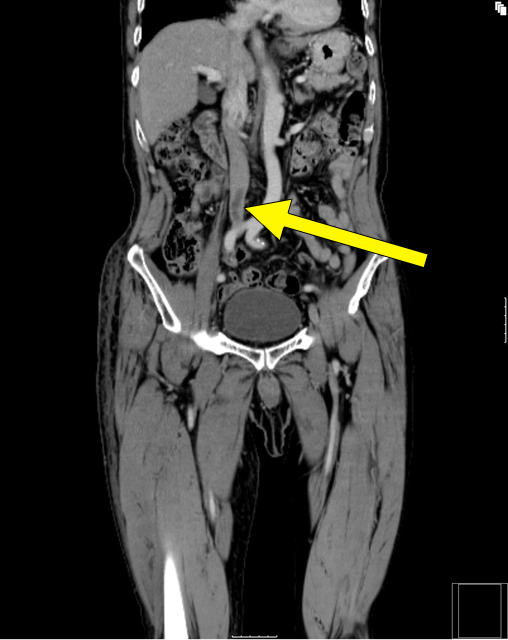

肺動脈CT

肺塞栓症では、下肢深部静脈にできた血栓が原因であることが多く見受けられます。当院では、塞栓源の検索も含め、下肢血管までの広い範囲を一度の造影検査で行っています。

| CT画像(矢印部のやや黒く見える部分が血栓) | 冠状断にて血栓を観察する | 下大静脈内の血栓 |